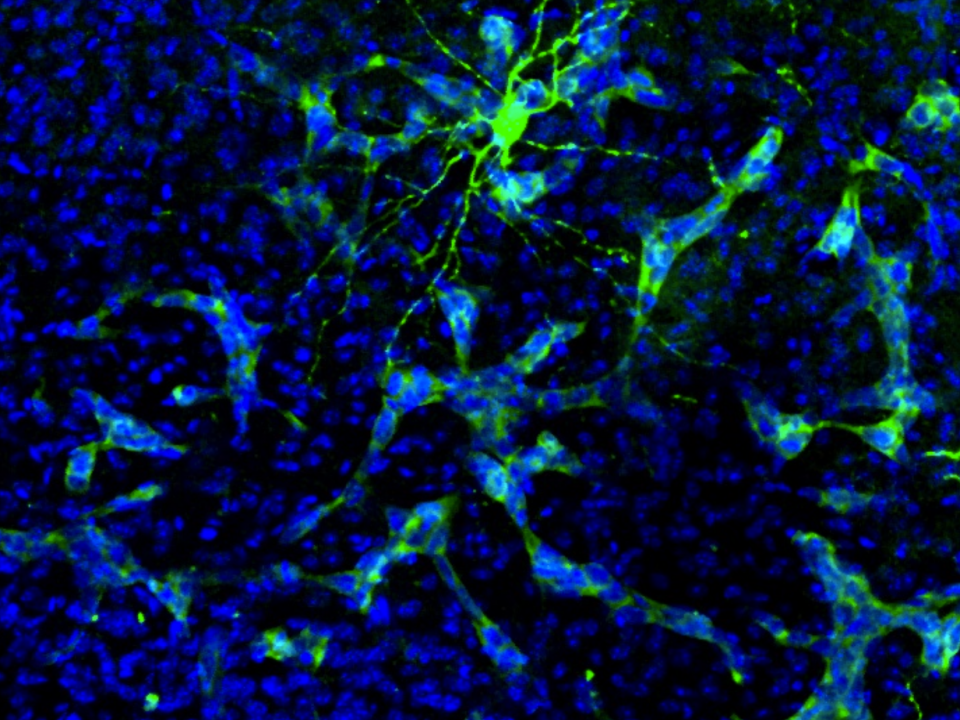

A pioneering study discovers that brain tumors 'hack' the communication between neurons

The researchers, from the CSIC and the CNIO, propose that cognitive loss in patients with brain metastasis may be due to the 'interferences' that cancer creates in neuronal circuits.